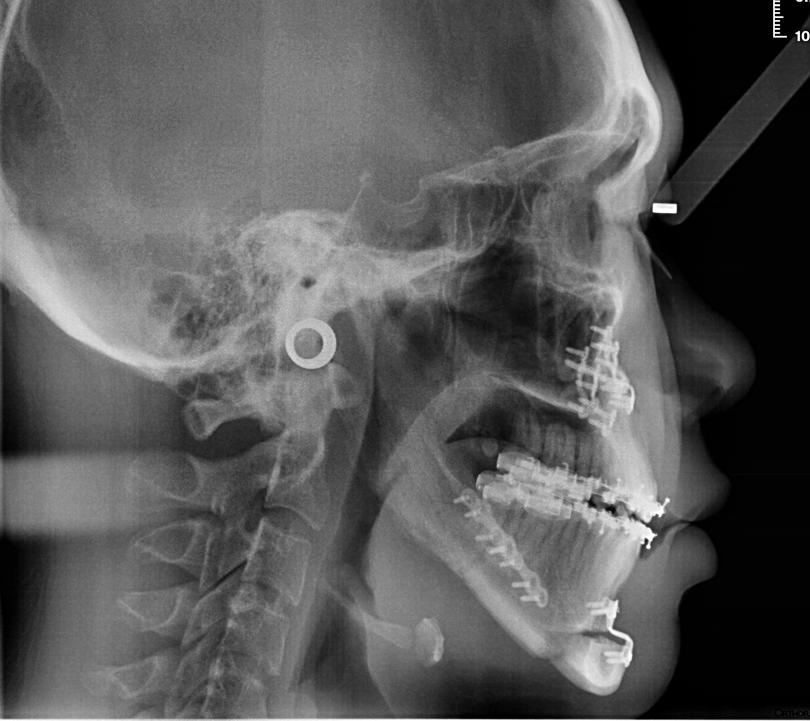

X-rays showing jaw misalignment and correction before and after orthognathic surgery respectively.

One bite at a time

When it comes to straightening crooked teeth, dental braces or retainers are the first go-to solution. However, for people with severe misalignment in their jaws, a more major intervention — such as orthognathic surgery — may be required.

Orthognathic surgery, also known as corrective jaw surgery, aims to correct deformities or misalignment of the upper and lower jaws. These deformities and misalignments can result in malocclusions, which refer to conditions where the upper and lower teeth are misaligned when the mouth is closed — common forms include underbites, overbites or open bites.

Orthognathic surgery can also address other conditions, such as facial injuries and severe obstructive sleep apnea (OSA). In cases of severe OSA, misaligned jaws can restrict the airway, leading to breathing difficulties. Surgery to reposition the jaws and widen the airway can ease breathing problems and alleviate OSA.

A multi-stage treatment process

Rather than a single procedure, orthognathic surgery is a comprehensive course of treatments combining both orthodontic and surgical approaches that can take years to complete. As orthognathic surgery is a major intervention, it is usually prescribed when patients experience difficulties in functional issues, such as chewing, biting or speaking properly.

According to Dr Leonardo Saigo, Consultant and Deputy Head, Department of Oral and Maxillofacial Surgery, National Dental Centre Singapore, patients who undergo orthognathic surgery typically

“At times, a surgery-first approach, where patients undergo orthognathic surgery without pre-operative orthodontic treatment, is possible,” said Dr Saigo. “This will reduce the treatment time significantly. However, the orthodontist and surgeon must assess if a patient is suitable for surgery first.”

Assessing suitability for surgery

While there is no age limit for orthognathic surgery, the treatment process for younger patients with underbites, overbites and open bites typically starts only after their period of growth has concluded. “Some patients who present early may be suitable for interceptive orthodontic treatment in the hope of avoiding the need for orthognathic surgery. However, it may not always be successful,” said Dr Saigo. “Most patients come in for treatment after their completion of growth as it will ensure post-surgical stability and lower risk of relapse.”

According to Dr Saigo, underbites have a higher incidence among Asians, affecting approximately 20 per cent of the population. If left untreated, severe underbites can lead

after

to ongoing biting issues or wearing out of teeth towards the back of the mouth at a faster rate. “Some patients may complain of difficulty articulating certain words due to the gap between the front teeth. Additionally, having a longer lower jaw may affect their self-esteem and confidence regarding their appearance,” said Dr Saigo. “We have had young patients who initially declined surgery due to various reasons, only to return for orthognathic surgery after a number of years, having realised that the condition actually has a direct and significant impact on their quality of life.”

The jaw correction process goes beyond a single operation, often involving both orthodontic and surgical treatments over years.

before